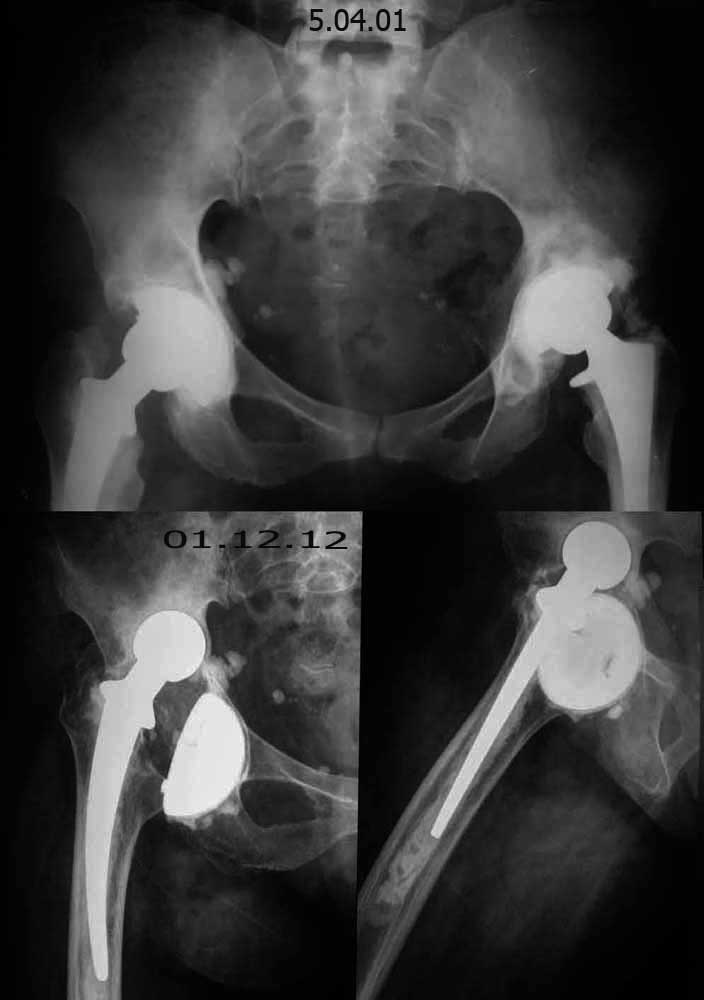

[Ortho] застарелый вывих эндопротеза тазобедренного сустава

> Уважаемые коллеги, помогите определиться  с  тактикой лечения! Больная Л.

> 56 лет,  20 лет страдает ревматоидным полиартритом.  В 1987 году выполнена

> операция- артропластика левого тазобедренного сустава по Кулишу. В 1997

> году оперирована - тотальное эндопротезирование правого тазобедренного

> сустава. В 1998 году оперирована - тотальное эндопротезирование левого

> тазобедренного сустава.  1,5 года назад больная упала, после чего стала

> отмечать боль в области правого тазобедренного сустава.

> Локально: правая нижняя конечность укорочена на 1-1,5см. по сравнению с

> левой. Движения в правом тазобедренном суставе: сгибание - 35-40&#186;,

> разгибание-10&#186;, отведение- 15&#186;, приведение-10&#186;, наружная

> ротация-20-25&#186;, внутренняя ротация-0&#186;.

> Движения в левом тазобедренном суставе: сгибание - 75-80&#186;,

> разгибание-15&#186;, отведение- 30&#186;, приведение-20&#186;, наружная

> ротация-25-30&#186;, внутренняя ротация-20&#186;.